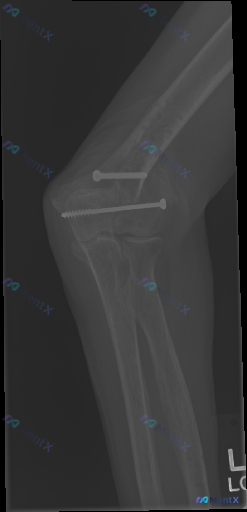

整理到一张肘关节侧位X光片的资料,先不说背景,大家第一眼能看到什么异常? 补充一下已知信息:这是一张术后随访片,再结合图像,有没有容易被忽略的解读陷阱或者需要重点警惕的风险点?